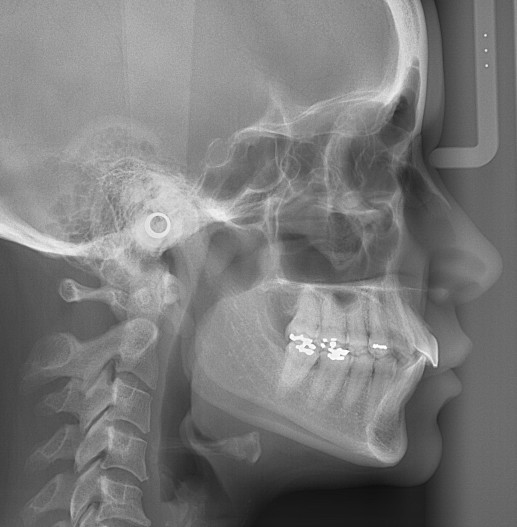

Die FRS-Auswertung (Abb. 1d) ergab eine distal-basale Kieferrelation nach WITS (2,6 mm) bei tendenzieller maxillärer Prognathie (SNA 86,5°). Aus der dentalen Analyse des FRS ging eine deutliche Anteinklination der Oberkieferinzisivi (IOK-NL 126,5°) und eine manifeste Anteinklination der Unterkieferinzisivi (IUK-ML 103,6°) bei stark verkleinertem Interinzisalwinkel (IOK-IUK 112,3°) hervor. Die vertikalen Parameter ergaben einen brachiofazialen Gesichtsschädelaufbau. Die Auswertung des OPG (Abb. 1e) zeigte eine adulte Dentition mit fehlenden dritten Molaren. Außerdem war eine extreme Mesialkrümmung der Wurzel 25 erkennbar. Es zeigte sich ein moderater generalisierter horizontaler Knochenabbau des Limbus alveolaris im Ober- und Unterkiefer von ca. 15 Prozent.